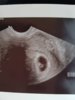

Og Exu er nå helt utelukket[emoji173] [emoji173] [emoji173] [emoji173] [emoji119] [emoji119] [emoji119] [emoji119] [emoji119] [emoji173] [emoji173] [emoji173] Endelig kan jeg slappe av og virkelig nyte jeg er gravid[emoji173][emoji175][emoji178][emoji177][emoji119][emoji87][emoji41][emoji1] Vi så hjerteslag og jeg er overlykkelig[emoji16] [emoji16] [emoji16] [emoji16] [emoji173] [emoji173] [emoji173] [emoji173]

for en lykke